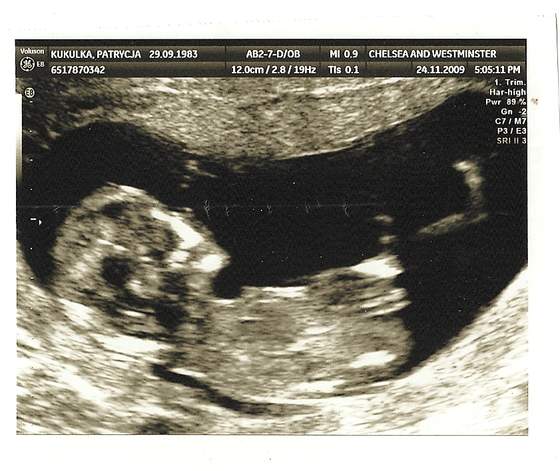

Przypominam, że dalej nasza forumowa mama potrzebuje Twojej pomocy 💖 Jeśli możesz wpłacić nawet drobną kwotę, to prosimy zrób to Kliknij